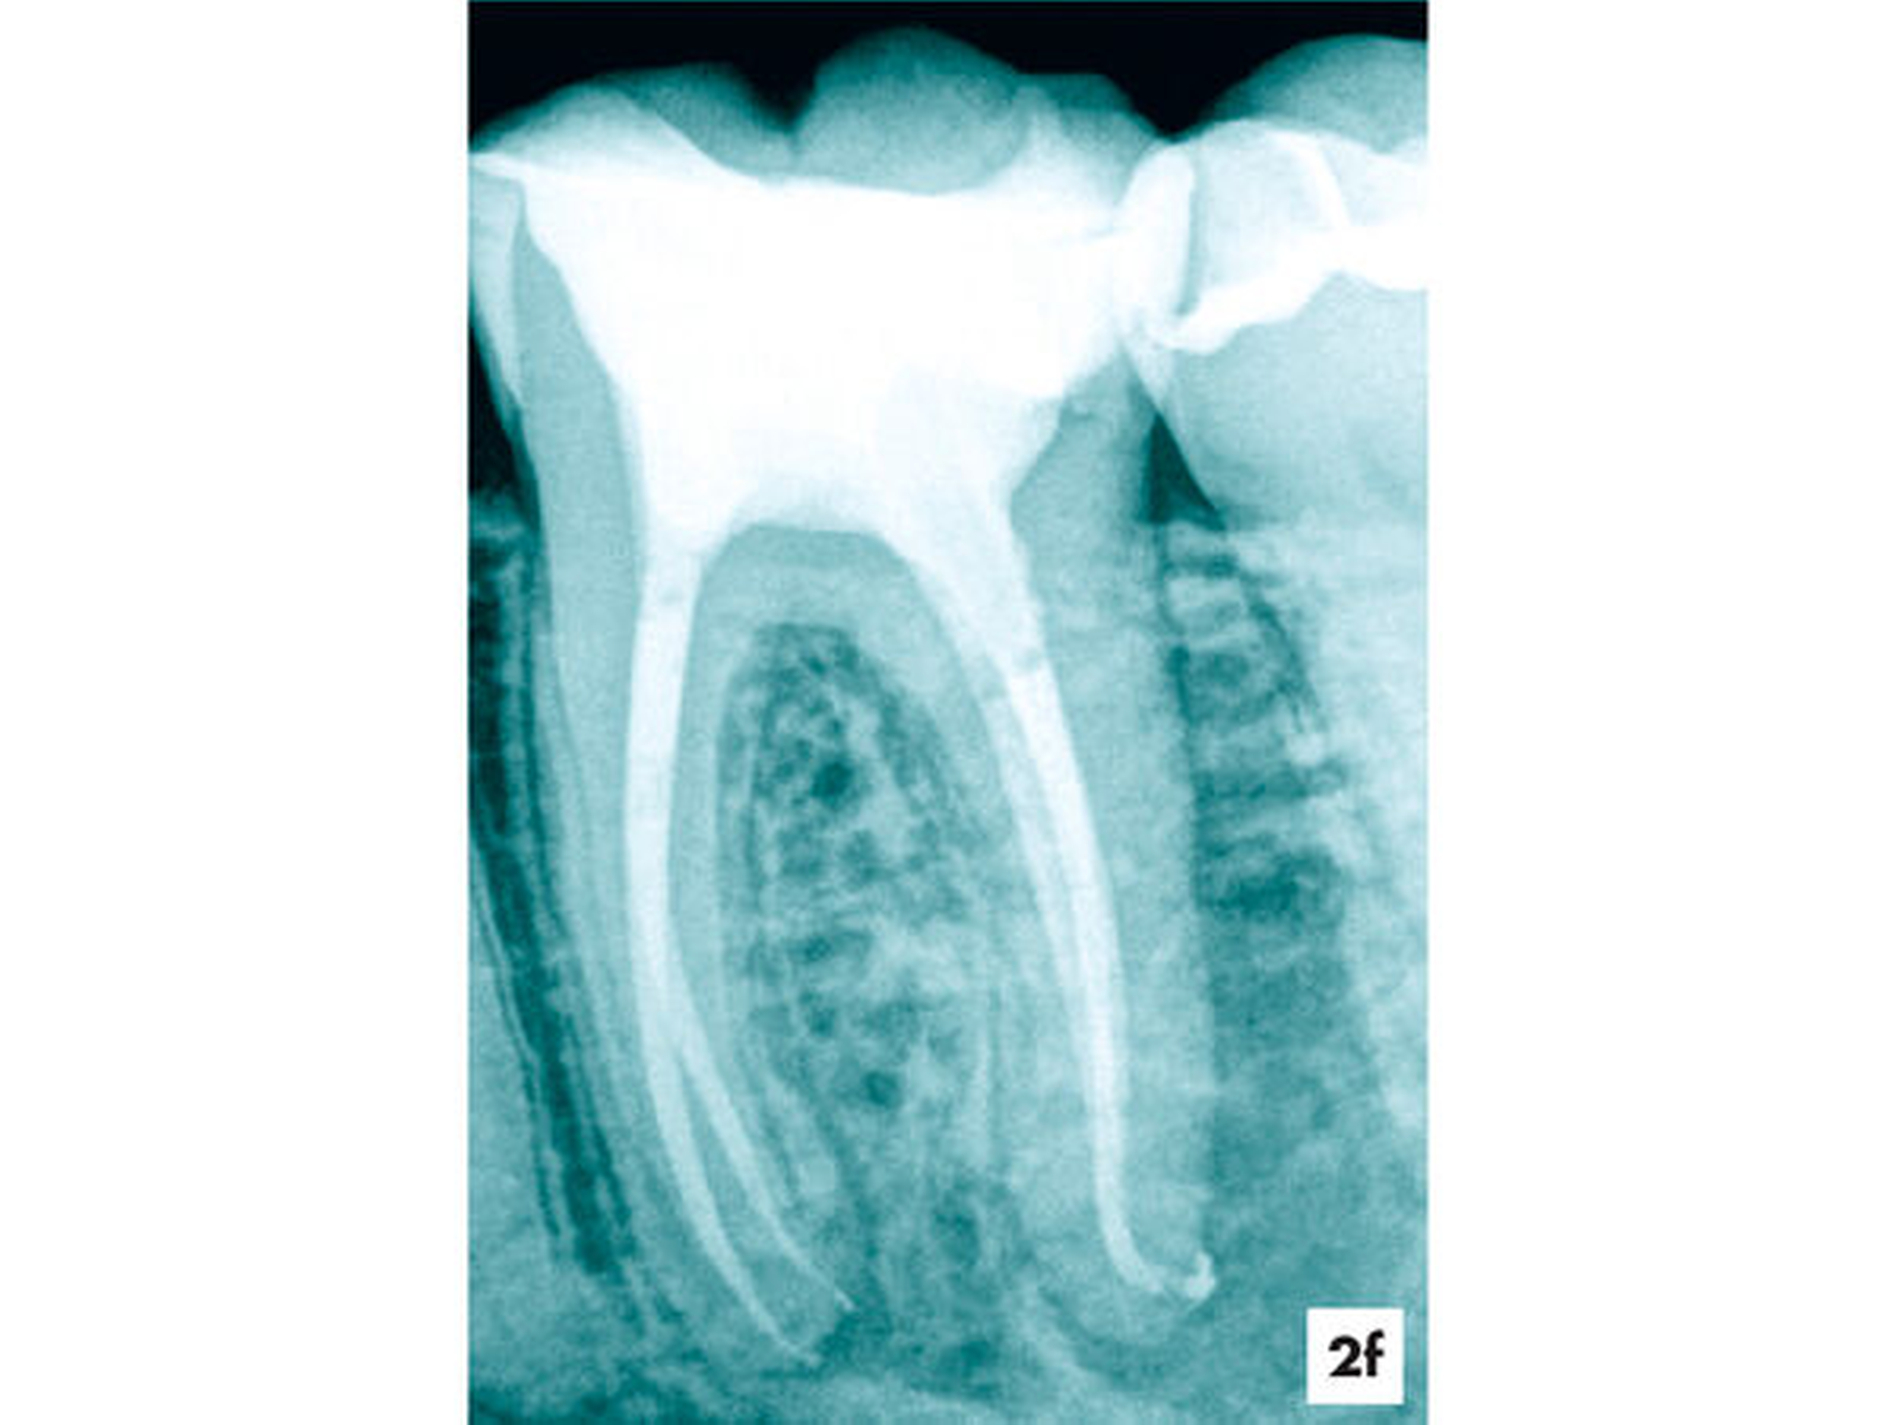

Fallbeispiel 2 (Abbildung 2)

Eine ehemals profunde Karies führte über mehrere Jahre zu einer degenerativen Pulpaerkrankung am Zahn 36. Röntgenologisch ließ sich eine Obliteration der Pulpakammer und des mesialen Wurzelkanalsystems erkennen. Distal lag eine periapikale Aufhellung vor, die klinisch mit einer Fistel assoziiert war (Abbildung 2a).

Unter absoluter Trockenlegung des Zahnes 36 mit Kofferdam erfolgte die Entfernung der Füllungsmaterialien. Im Verlauf der intrakoronalen Befundaufnahme und Diagnostik ließ sich bei 8- bis 16-facher Vergrößerung dunkel verfärbtes Dentin distal erkennen (Abbildung 2b). Innerhalb der Pulpakammer ließ sich ein dentinähnliches Hartgewebe zum Sekundärdentin differenzieren. Weichgewebige Einschlüsse am Rand ließen vermuten, dass es sich um eine reizgebundene Hartgewebeneubildung der Pulpa handelte (Abbildung 2c). Mit grazilen Rosenbohrern in absteigender Größe von ISO 012 bis 005 ließ sich das Hartgewebe sicher entfernen, so dass die mesialen Wurzelkanaleingänge für eine mechanische Erweiterung zugänglich waren (Abbildung 2d).

Während sich mesial vitales Pulpagewebe erhalten konnte, lag distal eine Pulpanekrose vor. Als Folge der Reizdentinbildung kam es auch in der distalen Wurzel zu einer Unterteilung in drei Wurzelkanäle, die bei 16-facher Vergrößerung substanzschonend erweitert, desinfiziert und gefüllt werden konnten (Abbildung 2e).

Zwei Tage nach Abschluss der einzeitigen Therapie war die Fistel verschlossen und zum 6-Monats-Recall ließ sich bereits eine deutliche Verringerung der periapikalen Aufhellung nachweisen (Abbildungen 2f und 2g).